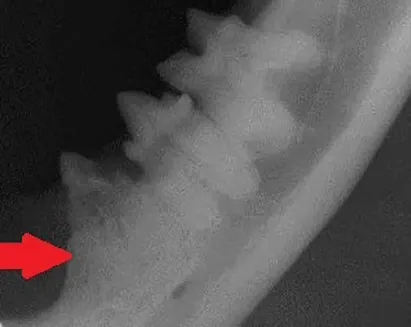

Dental radiograph of the left mandibular premolar teeth in a dog showing a classic example of canine tooth resorption.

Diagnosis: When tooth resorption (TR) is seen on routine dental radiographs, the next step is to carefully evaluate the tooth with a dental explorer along the gingival margin and look for clinical evidence of resorption (a sticky or rough area at or just below the gum line).

Treatment: If clinical evidence of resorption is found, the tooth should be extracted. If there is no clinical evidence of a lesion, radiographic monitoring is acceptable, as root resorption is reported to be non-painful in humans.

Extractions of these teeth can be challenging due to the high degree of ankyloses and resorption, and referral to a veterinary dentist is strongly recommended. Crown amputation is not a recognized treatment for these lesions; however, the first premolar tooth (red arrow) may be a candidate, as the end of the root appears isolated from the rest of the tooth and completely surrounded by new bone.